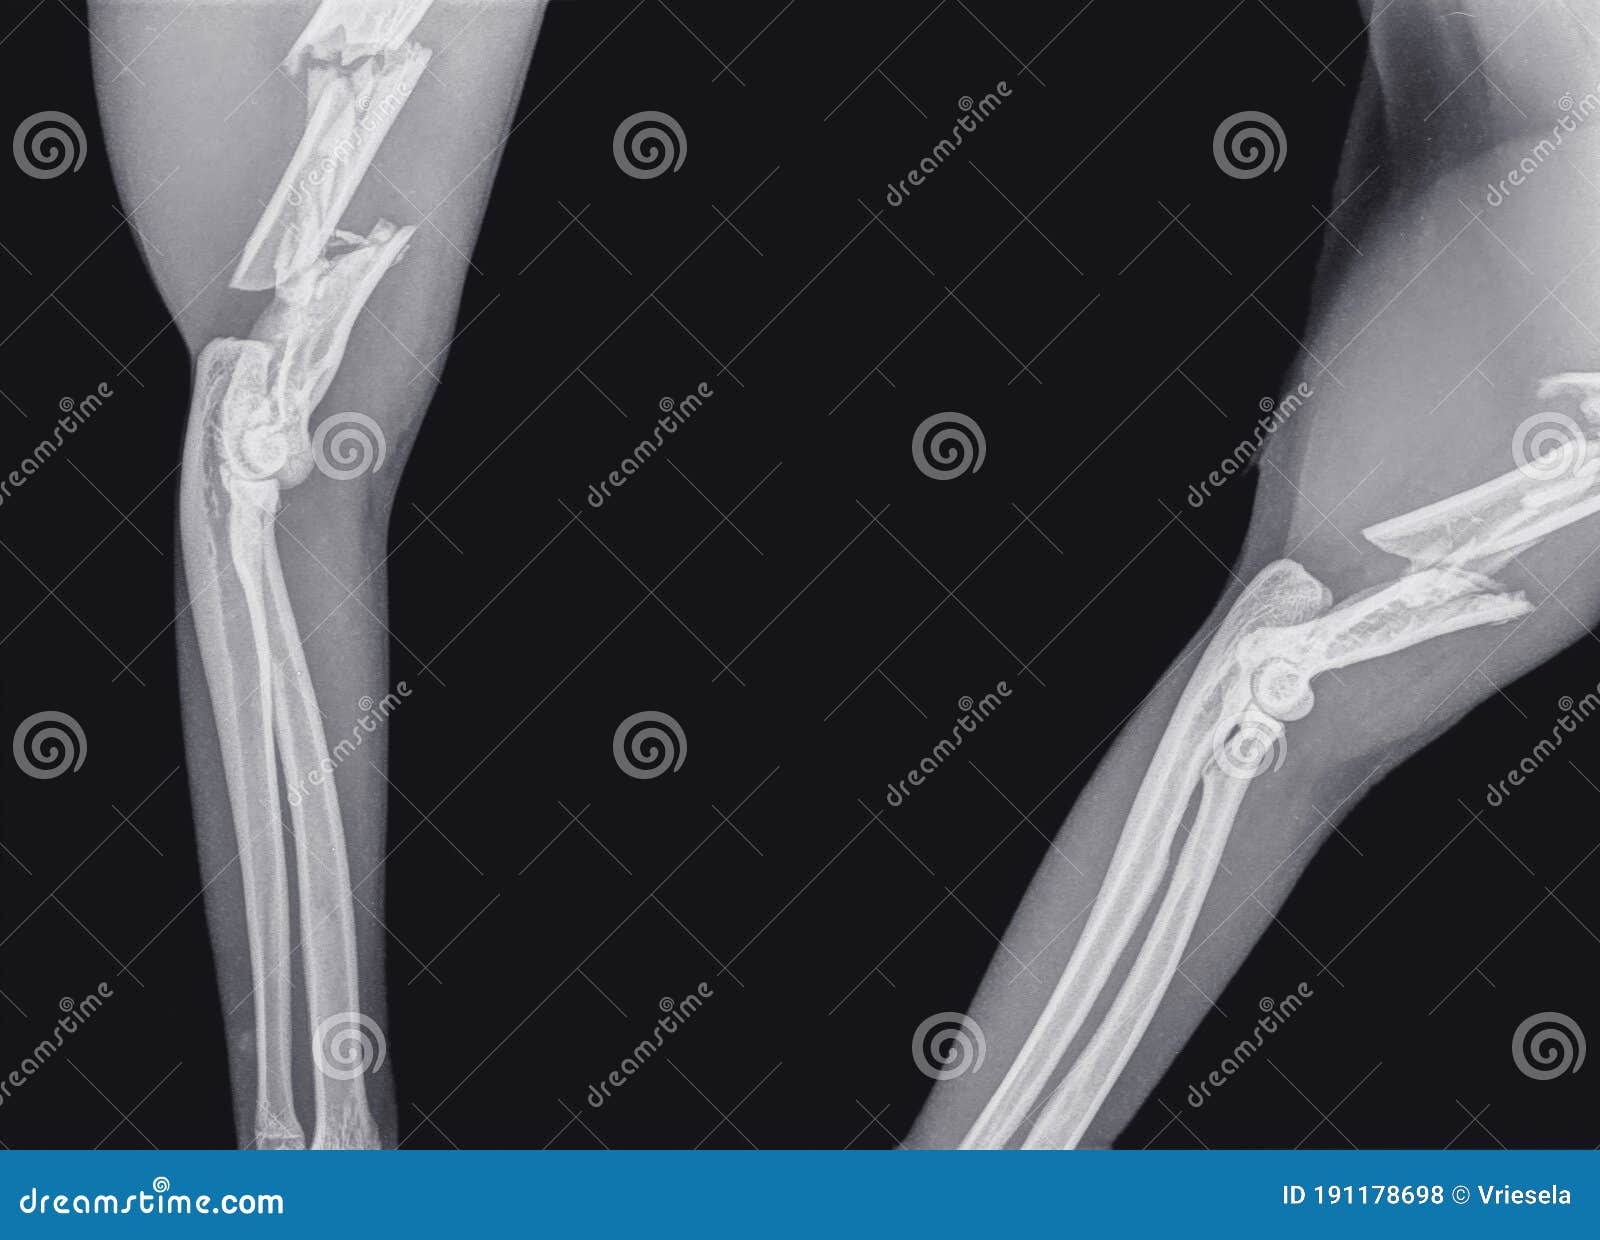

X Ray Image Of Broken Arm Bone Anatomy Of Fracture Humerus Stock Photo Arm Bone Humerus Fracture a humerus fracture is a broken bone in the upper arm that connects the shoulder to the elbow. a humerus fracture is the medical name for breaking the bone in your upper arm (your humerus). a humerus fracture is a break of the humerus bone in the upper arm. We’ll go over the locations of each type.. Arm Bone Humerus Fracture.

Fracture of the Upper Arm Bone Humerus of a Cat Stock Photo Image of Arm Bone Humerus Fracture There are several types of humerus fractures, depending on the location of the break. We’ll go over the locations of each type. what is a broken arm? Symptoms may include pain, swelling, and bruising. a humerus fracture is a break in the large bone of your upper arm. A broken arm is a bone fracture (broken bone) in. Arm Bone Humerus Fracture.